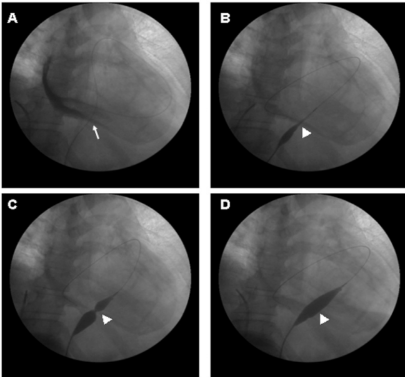

Hình 1. Quá trình nong bóng màng ngoài tim dưới màn tăng sáng